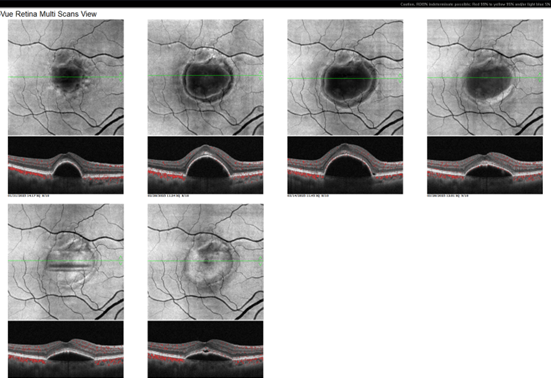

A 77-year-old male presented to my clinic complaining of distortion in his right eye. He was found to have exudative macular degeneration in his right eye and dry macular degeneration in his left. He was treated with injections of Anti-VEGF and was doing quite well with monthly injections for nine months with vision of 20/25 and normal eye pressure, at which point his response dwindled and the CNV enlarged in size despite monthly injections (Figure 1). The first image shows his PED/CNV on monthly injections; the second scan is one month later. Despite one of the stronger anti-VEGF drugs, his vision dropped to 20/40 in his right eye. The patient felt his vision improved immediately after injections and got worse again sooner than one month. Due to his lack of response to the standard treatment, we attempted to increase injection frequency to every two weeks instead of four. He finally improved once injections were given every two weeks as shown in the fourth scan.

OCT and OCT Angiography were performed using the Optovue Solix by Visionix to evaluate the structural abnormalities and better characterize this patient’s neovascularization. OCT Angiography confirmed a choroidal neovascular complex under the enlarging pigment epithelial detachment (Figure 1). Figure 2 shows the CNV within this PED, and Figure 3 shows the en face OCT demonstrating worsening and resolution. The comparison tool on the Optovue Solix machine was instrumental in assessing treatment response and assuaging the patient’s concerns that he would continue to worsen. Once he saw improvement, he felt more comfortable, and we continued the treatment course. His PED continues to improve, and his vision is back to his baseline of 20/25.

Figure 1 - OCT Angiography confirmed a choroidal neovascular (CNV) complex under the enlarging pigment epithelial detachment. The images show the patient’s CNV enlarging in size despite monthly Anti-VEGF injections.